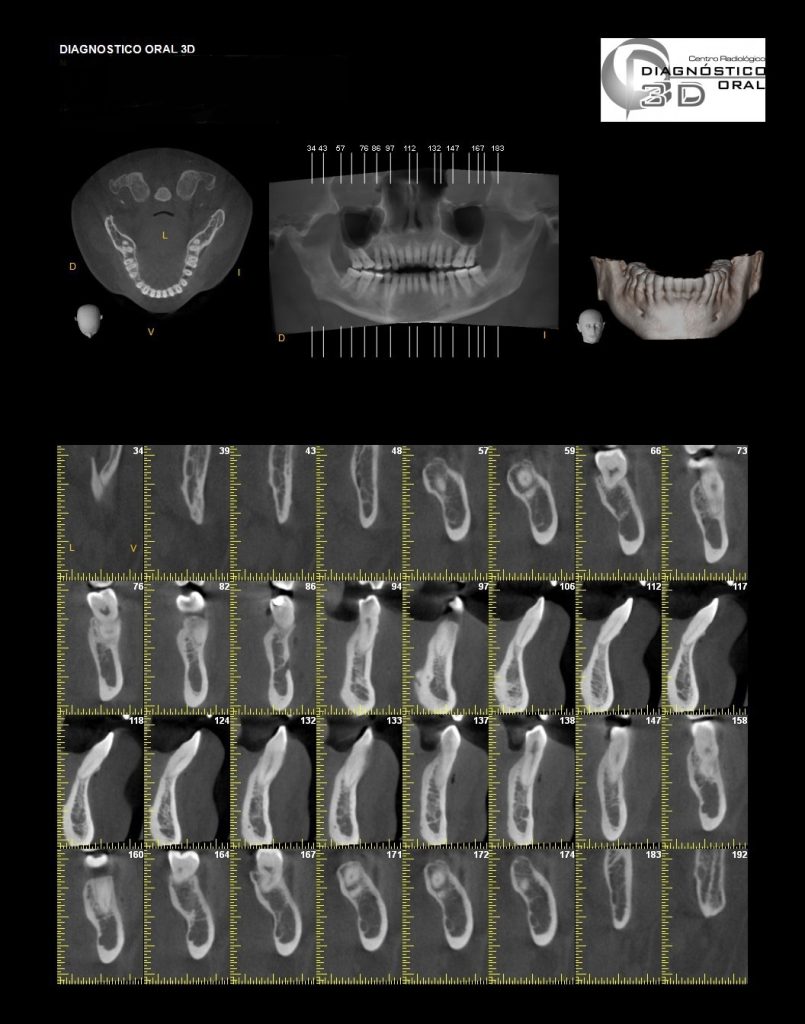

El Centro Radiológico Diagnóstico Oral 3D, es una empresa antioqueña que ofrece a sus pacientes desde el año 2009, tecnología de vanguardia en radiografías tridimensionales con calidad fotográfica. Las posibilidades para mejorar la eficacia en los diagnósticos bucales son evidentes, también lo son las posibilidades de manipulación de imagen. El sistema de imágenes en 3D ofrece detalles sin precedentes, convirtiéndola en la opción idónea para la mayoría de aplicaciones odontológicas, incluyendo implantes, tratamiento de conductos, ortodoncia, odontopediatría, periodoncia y cirugía

El mayor beneficiado con el uso de esta tecnología es el paciente, el cual podrá ser evaluado en todas sus dimensiones con una baja dosis de radiación, con un costo accesible y sin contaminar  el medio ambiente. Dependiendo de la necesidad del paciente, hay varios tipos de tomografías y los especialistas en el área odontológica hacen uso de ellas según su especialidad.

La radiología oral especializada es fundamental para una práctica dental integral, proporcionando información específica que influye en la toma de decisiones clínicas y mejora los resultados del tratamiento para los pacientes

Aplicaciones Clínicas:

Diagnóstico de caries y enfermedades periodontales

Evaluación de patologías dentales y maxilofaciales

Planificación de tratamientos ortodónticos y ortognáticos

Implantología dental

Diagnóstico de traumatismos dentales y maxilofaciales

Detección de lesiones quísticas y tumorales

Evaluación pre y postoperatoria de cirugías maxilofaciales